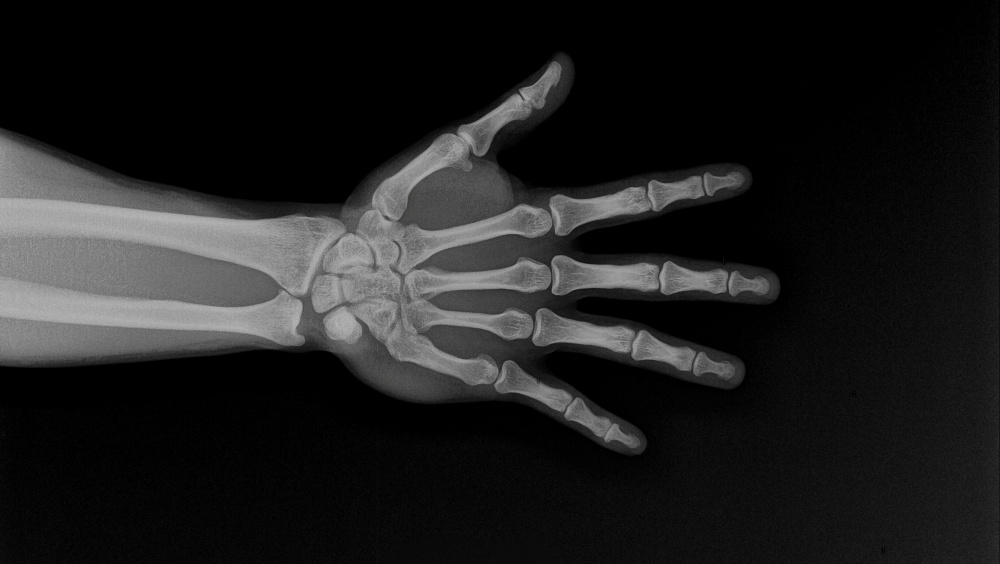

Микропластик обнаружен в человеческих костях — и он их ослабляет

Микропластик находят не только в океанах и на пляжах. Эти крошечные частицы обнаруживаются и внутри человеческого тела, включая мозг, сперму, легкие и кровеносные сосуды. Пластик попадает в организм через воздух, воду и пищу. Шины, текстиль, упаковка и выброшенные предметы — все это вносит мельчайшие частицы в воздух, почву и воду. Мелкие частицы могут перемещаться с кровотоком и оседать в тканях.

Новые исследования показывают, как микропластик могут влиять на здоровье костей и костного мозга. Исследователи из Бразилии, Канады и Франции провели метаанализ 62 исследований, чтобы объяснить воздействия микропластика на костную ткань. Работа вышла в Osteoporosis International. Один из ведущих авторов, Родриго Б. Оливейра из Государственного университета Кампинас в Бразилии: «Например, исследования in vitro показали, что микропластик ухудшает жизнеспособность клеток, ускоряют их старение и вызывают воспаление». При этом средний уровень отложения микропластика в костях составляет десятки ч

При этом средний уровень отложения микропластика в костях составляет десятки частиц на грамм.

Исследование описывает изменения в поведении клеток, важные для прочности костей. Сигналы, которые способствуют созреванию клеток, оказались ослаблены, в то время как сигналы, способствующие разрушению костей, — наоборот.

В некоторых моделях баланс склоняется в пользу остеокластов — клеток, которые удаляют старую кость. Слишком интенсивное удаление, называемое резорбцией кости, со временем делает скелет более хрупким.

Клетки, подвергшиеся воздействию микропластика, могут выделять воспалительные молекулы, что сбивает процесс обновления костей. Это может привести к повышенному уровню химического стресса внутри клеток костной ткани.

Исследователи также сообщают, что микропластик может проникать в более глубокие отделы костей, включая костный мозг. Нарушение работы костномозгового аппарата может негативно сказаться как на формировании кровяных клеток, так и на обновлении костей.

Возраст и гормональные изменения уже ведут к потере костной массы. Дополнительный стресс от микропластика может усугубить проблему, особенно у людей с другими факторами риска. Международный фонд остеопороза прогнозирует, что число переломов тазобедренного сустава почти удвоится к 2050 году по сравнению с 2018.